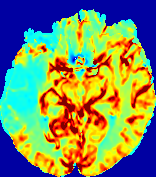

LesionRefer to captionRefer to captionRefer to captionRefer to captionRefer to captionRefer to caption𝐕rgbsubscript𝐕𝑟𝑔𝑏{\bf{V}}_{rgb}Refer to captionRefer to captionRefer to captionRefer to captionRefer to captionRefer to caption𝐕2subscriptnorm𝐕2{\|\bf{V}}\|_{2}Refer to captionRefer to captionRefer to captionRefer to captionRefer to captionRefer to captionRefer to caption3.53.53.52.82.82.82.12.12.11.41.41.40.70.70.70.00.00.0(mm/s)𝑚𝑚𝑠(mm/s)D𝐷DRefer to captionRefer to captionRefer to captionRefer to captionRefer to captionRefer to captionRefer to caption0.0200.0200.0200.0160.0160.0160.0120.0120.0120.0080.0080.0080.0040.0040.0040.0000.0000.000(mm2/s)𝑚superscript𝑚2𝑠(mm^{2}/s)Slice #1Slice #2Slice #3Slice #4Slice #5Slice #6

Figure 4: PIANO feature maps for another patient in the ISLES 2017 training set, where the lesion is located in the right hemisphere. Top row: segmented stroke lesion region (white) on different slices. The corresponding slices for the PIANO feature maps are shown in the following rows.

For a better insight into an estimated velocity field 𝐕𝐕{\bf{V}} and diffusion field 𝐃𝐃{\bf{D}}, we compute the following maps: (1) 𝐕rgbsubscript𝐕𝑟𝑔𝑏{\bf{V}}_{rgb}: Color-coded orientation map of 𝐕=(Vx,Vy,Vz)T𝐕superscriptsuperscript𝑉𝑥superscript𝑉𝑦superscript𝑉𝑧𝑇{\bf{V}}=(V^{x},V^{y},V^{z})^{T}, obtained by normalizing 𝐕𝐕{\bf{V}} to unit length and mapping its 3 components to red, green, blue respectively; (2) 𝐕2subscriptnorm𝐕2\|{\bf{V}}\|_{2}: 222 norm of 𝐕𝐕{\bf{V}}; (3) D𝐷D: scalar field in Eq. 5.

Fig. 3 and Fig. 4 show the PIANO feature maps estimated from two ISLES 2017 patients: all are highly consistent with the lesion in both cases. Details of the blood flow trajectories are revealed in 𝐕rgbsubscript𝐕𝑟𝑔𝑏{\bf{V}}_{rgb} by the ridged patterns and the sharp changes of colors in the unaffected (right) hemisphere, while the flat patterns appearing within the lesion provide little directional information about the velocity and indicate low velocity magnitudes. Velocity magnitudes are more directly visualized via 𝐕2subscriptnorm𝐕2\|{\bf{V}}\|_{2}, from which one can easily locate the lesion where 𝐕2subscriptnorm𝐕2\|{\bf{V}}\|_{2} is low. D𝐷D also indicates lower diffusion values in the lesion, though with less contrast potentially due to the fact that it captures the accumulated effect of CA diffusion at the voxel-level.